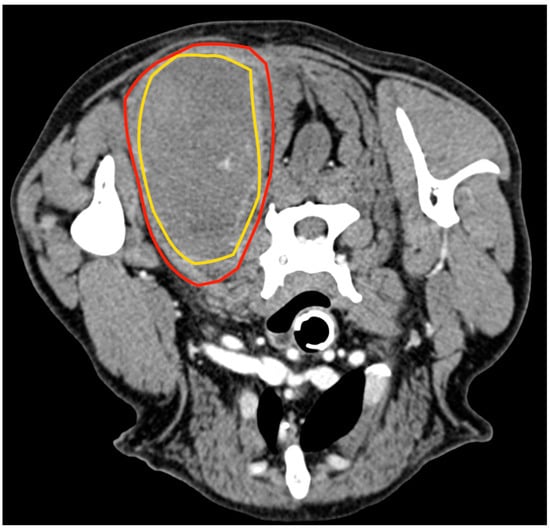

3.3. Case 3

An 8-year-old 35 kg spayed female mixed breed was referred for a 10 cm mass localised between the dorsal neck and the left scapular region, which had been noted a week earlier and had grown rapidly. At clinical examination, the mass appeared as a painful, firm, subcutaneous lesion adhering to the underlying tissues. No regional lymphadenopathy was detected. The cytology performed by the referring veterinarian was indicative of a malignant mesenchymal sarcoma. Total body CT confirmed the anatomic confinement of the tumour to the dorsal surface of the splenius capitis (Figure 5). No other anomalies were found based on the CT exam.

Figure 5.

Tomographic appearance of the neoplasm within the splenius capitis muscle between the seventh cervical vertebra and the medial surface of the scapula. The yellow line delimitates the tumours, and the red line is the splenius capitis muscle.